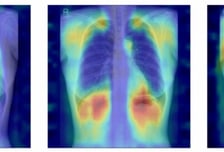

흉부 엑스레이만 찍어도 '골다공증' 알 수 있다…AI 개발한 서울대병원

서울대병원이 흉부 X선만으로 정상·골감소증·골다공증을 분류하는 인공지능(AI) 모델을 개발했다. 흉부 X선에는 갈비뼈·쇄골·척추 등 골절과 밀접한 뼈 구조가 포함돼 있어 이를 활용하면 별도 골밀도 검사 없이도 골다공증을 조기에 확인할 수 있는 '기회 검진(opportunistic screening)'이 가능하다. 연구팀은 특히 AI가 실제로 어떤 뼈 구조를 근거로 판단하는지를 수치로 검증하는 평가 체계를 마련해, 임상에서도 신뢰할 수 있는 의료 AI의 가능성을 제시했다. 골다공증은 뼈의 양이 줄고 구조가 약해지면서 골절 위험이 높아지는 질환으로, 고령화와 함께 환자가 빠르게 증가하고 있다. 그러나 표준검사인 DXA(골밀도 검사)는 장비 접근성 등의 문제로 충분히 시행되지 못하는 경우가 많다. 반면 흉부 X선은 대부분의 건강검진에서 이미 촬영되므로, 이를 활용해 골다공증 여부를 함께 평가할 수 있다면 조기 진단의 새로운 대안이 될 수 있다. 다만 지금까지의 AI 모델은 예측 과정이 명확하게 설명되지 않는 '블랙박스' 문제 때문에 임상 적용에 어려움이 있었다.